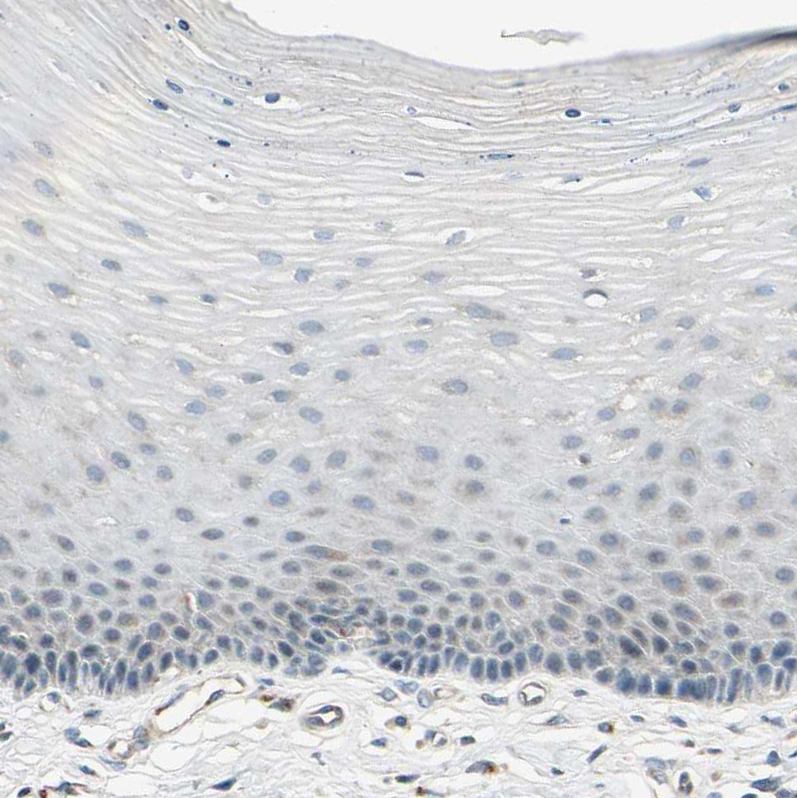

Immunohistochemistry analysis in human lung and cervix, uterine tissues using HPA007884 antibody. Corresponding ABCA3 RNA-seq data are presented for the same tissues.